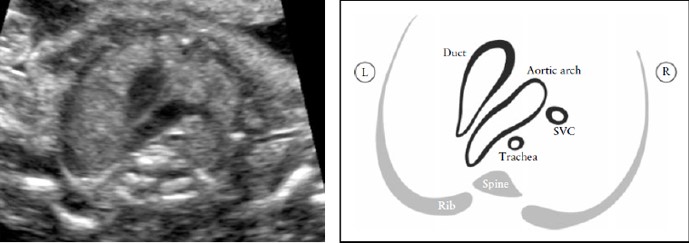

В этой проекции поперечная дуга аорты лучше видна («срез дуги аорты»), а также акцентируется ее взаиморасположение по отношению к трахее. Обычно трахея идентифицируется, как гиперэхогенное кольцо, окружающее маленькое жидкостное пространство. Дуга артериального протока и дуга аорты расположены слева от трахеи и образуют V-образную форму, так как обе они сливаются в нисходящую аорту (Рисунок 8). Дуга аорты является более краниальной, чем дуга артериального протока, поэтому для одновременной визуализации обеих дуг, потребуются некоторое отклонение датчика от плоскости, параллельной проекции четырех камер.

Рисунок 8. Срез через три сосуда и трахею (3VT). Этот срез демонстрирует наилучшим образом взаиморасположение дуги аорты по отношению к трахее. В нормальном сердце дуга аорты и дуга артериального протока располагаются слева от трахеи, образуя так называемое “V”- соединение. L-левый, R-правый; SVC-верхняя полая вена.

Проекция трех сосудов и трахеи дает возможность обнаружить такие пороки развития сердца как коарктация аорты, правосторонняя дуга аорты, удвоение дуги аорты и образование сосудистого кольца.